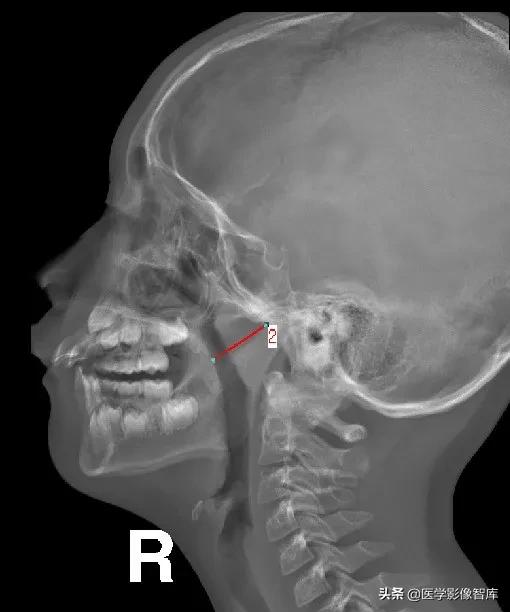

鼻咽侧位片的测量方法(二)

鼻咽后气道宽度(PAS)

软腭表面与腺样体表面最凸点之间有效气道宽度

作为PAS宽度 (图中a’),是鼻咽最小气道宽度

PAS宽度参考值:

- >10mm 属正常范围

- 6~10mm 腺样体生理性或中度肥大

- ≤5mm 腺样体重度肥大

- PAS≤3mm 患儿多有张口呼吸

- 有文献报道认为当A/N值≥0.71,PAS≤3mm可作为手术指征。